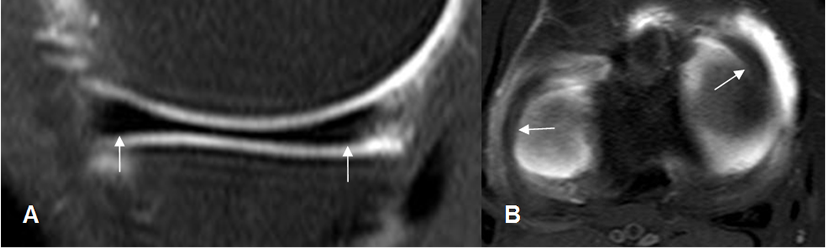

Fig 32. Ligamento transverso normal.

A: RM sagital en T1 y B: RM axial en T2. Estructura hipointensa en todas las secuencias, que une los meniscos en su parte anterior.

El cartílago articular es una estructura de bordes regulares y señal de intensidad (SI) homogénea, hipo o hiperintensa, según la secuencia elegida. (13). Las secuencias en T1 tienen buena sensibilidad para detectar lesiones condrales. (14).

Utilizando secuencias en T1 FS 3D FLASH, el cartílago muestra un aspecto trilaminar, con regiones superficial y profunda delgadas e hiperintensas y otra región media de señal intermedia. (15). (Fig 34 y 35).

Fig 34. Cartílago articular normal.

RM sagital en T1. Cartílago normal con señal intermedia y homogénea.

Fig 35. Cartílago patelar normal.

A: RM axial en T2. Cartílago normal, con señal homogénea e hipointensa.

B: RM axial 3D en T1 STIR. Cartílago hiperintenso y de aspecto trilaminar.